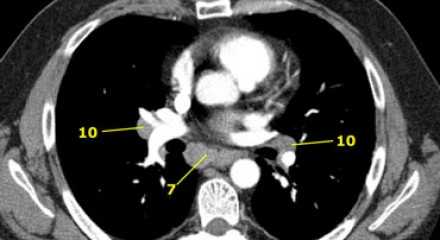

7. Подкаринальные лимфатические узлы

Эти лимфатические узлы расположены ниже уровня бифуркации трахеи (карины), но не относятся к нижнедолевым бронху и артерии. Справа они располагаются каудальнее нижней стенки промежуточного бронха. Слева они располагаются каудальнее верхней стенки нижнедолевого бронха. Слева лимфатический узел 7 группы справа от пищевода.

10. лимфатические узлы корня легкого

Лимфатические узлы корня расположены проксимальнее долевых узлов, но дистальнее медиастинальной дупликатуры и узлов промежуточного бронха справа.

Все лимфатические узлы 10-14 групп являются N1 узлами, так как они находятся вне средостения.